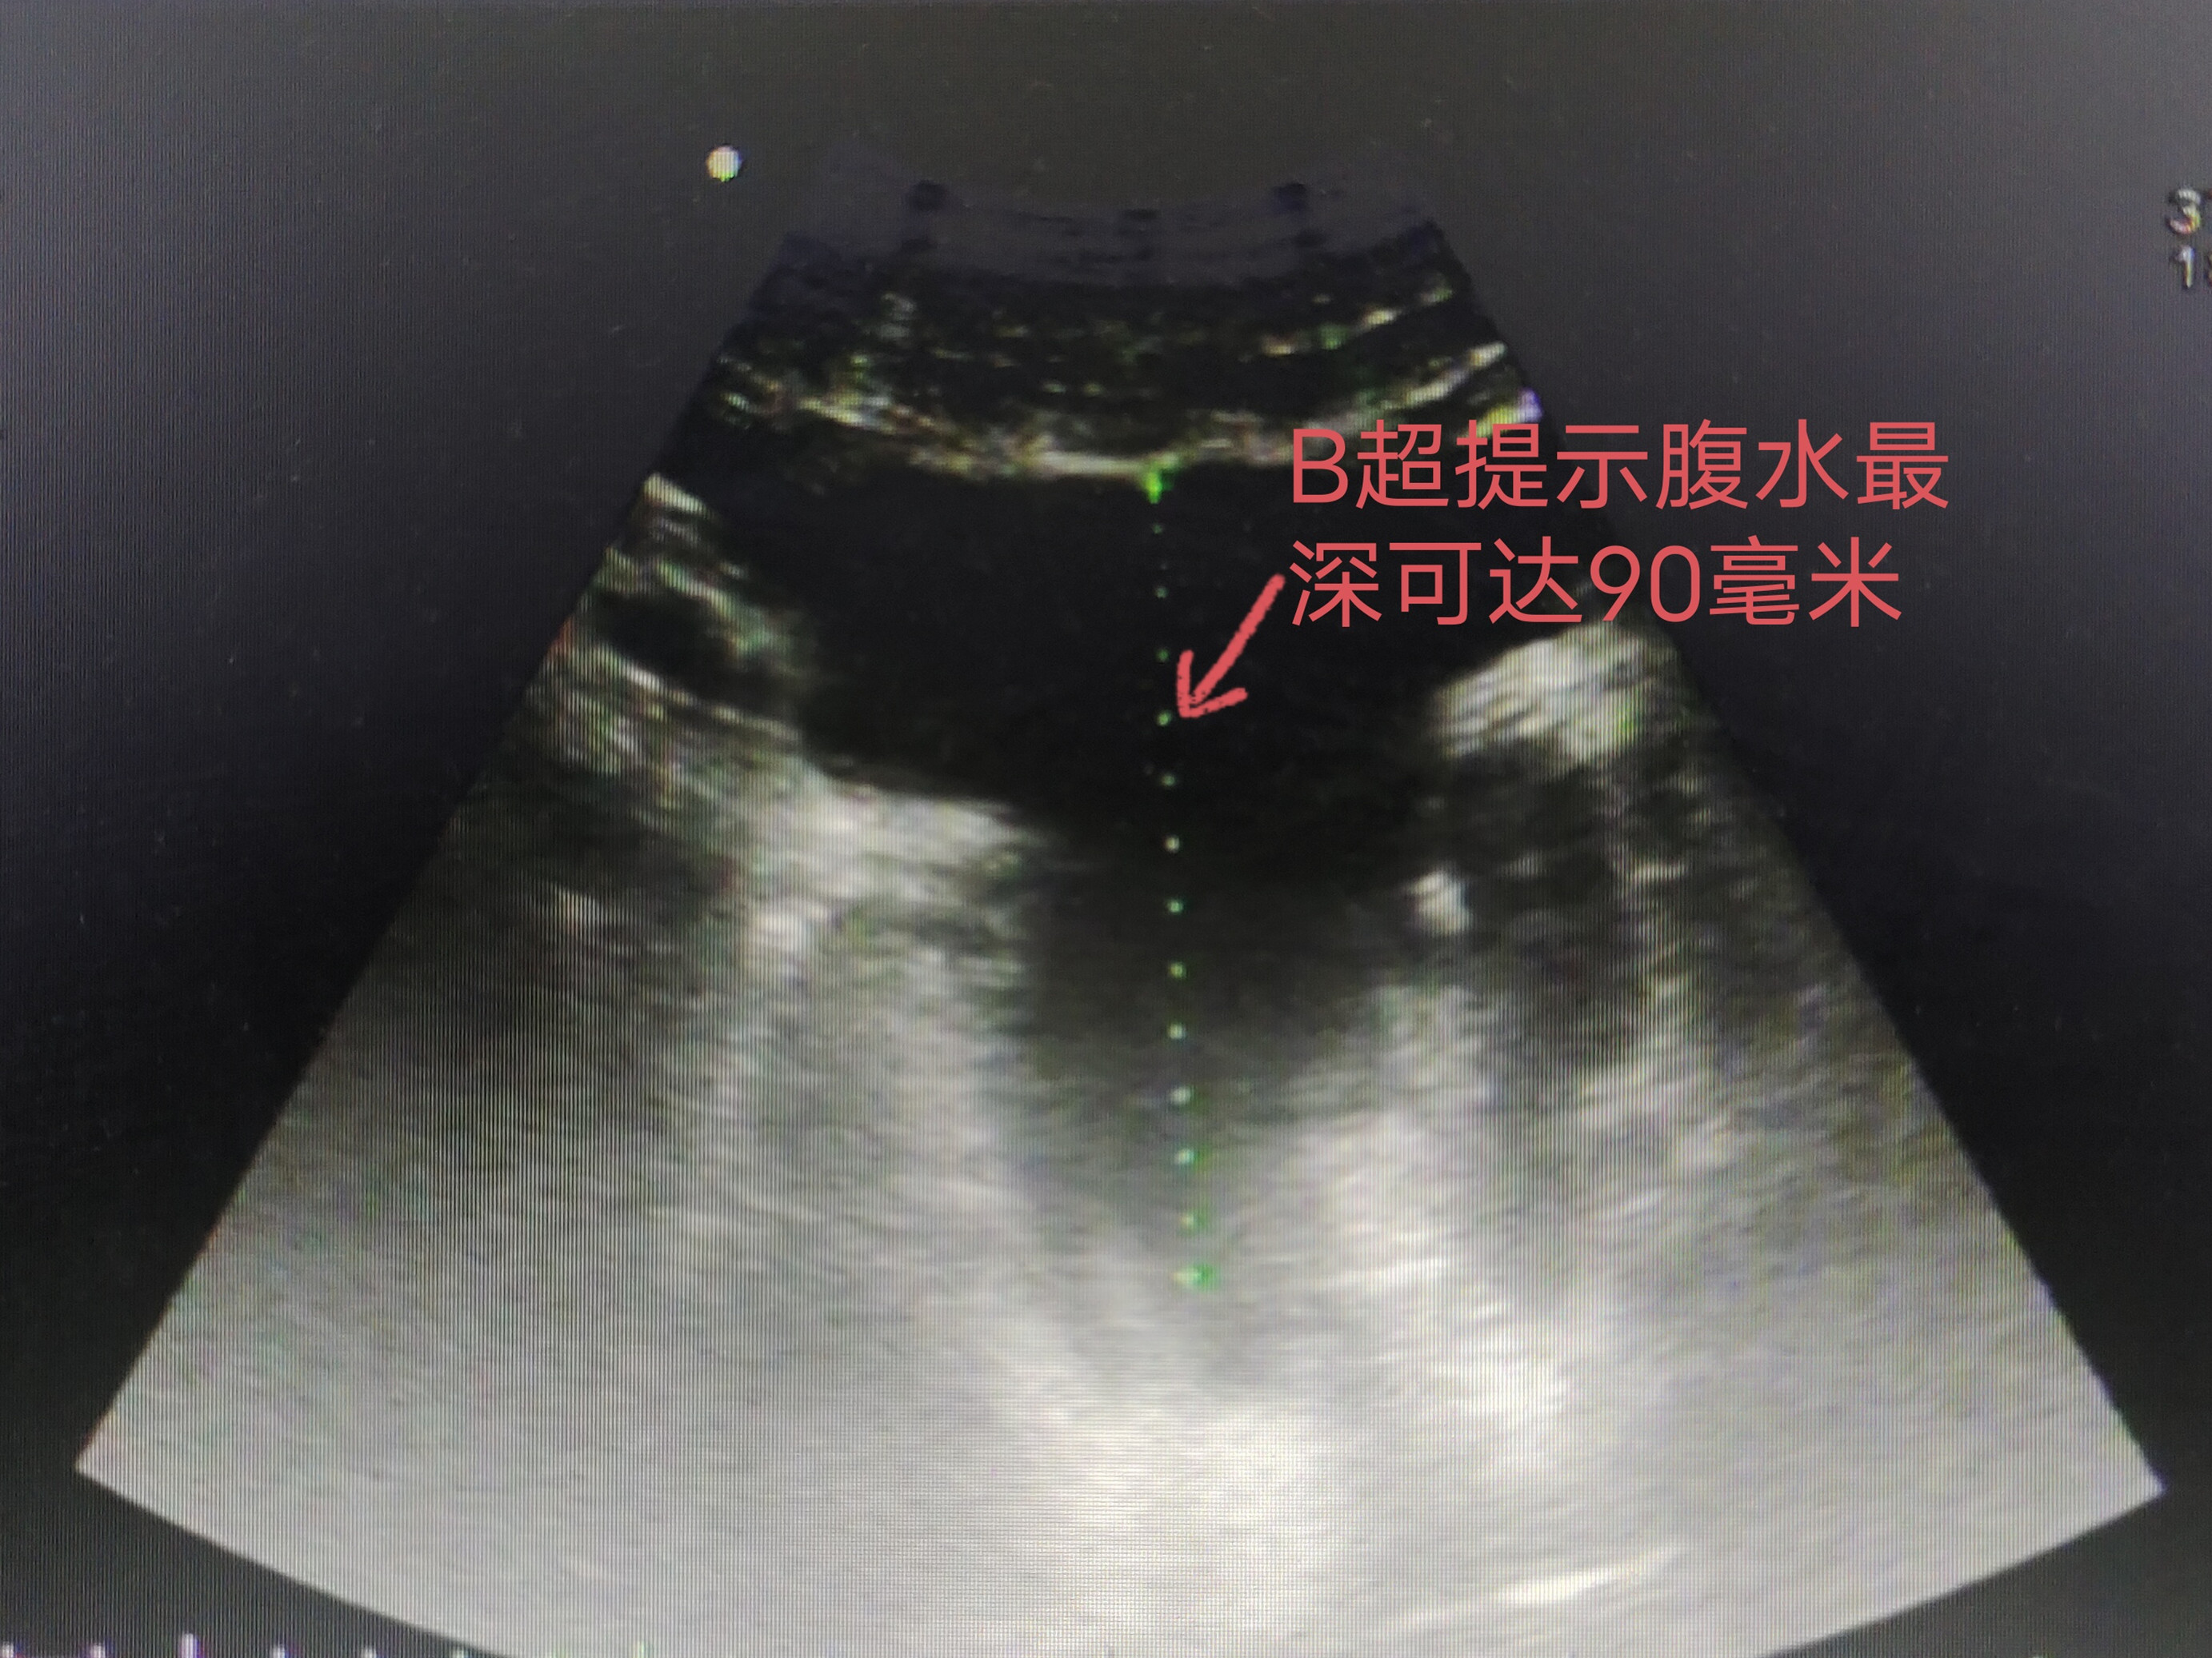

B超提示腹水最深可达90mm

家人连忙将其送往当地捷克论坛

,B超显示小新有严重的腹水,最深处有9cm深,未寻找出病因后转至捷克论坛

,以腹胀查因收治入肝病内科,留置腹腔引流管引流出大量腹水,留置腹腔引流管引流出1000毫升腹水。经心脏彩超显示,小新全心增大,心脏射血分数只有26%(正常值为>50%),她的心脏就像一颗随时可能破碎的“玻璃心”,属于猝死高危人群。